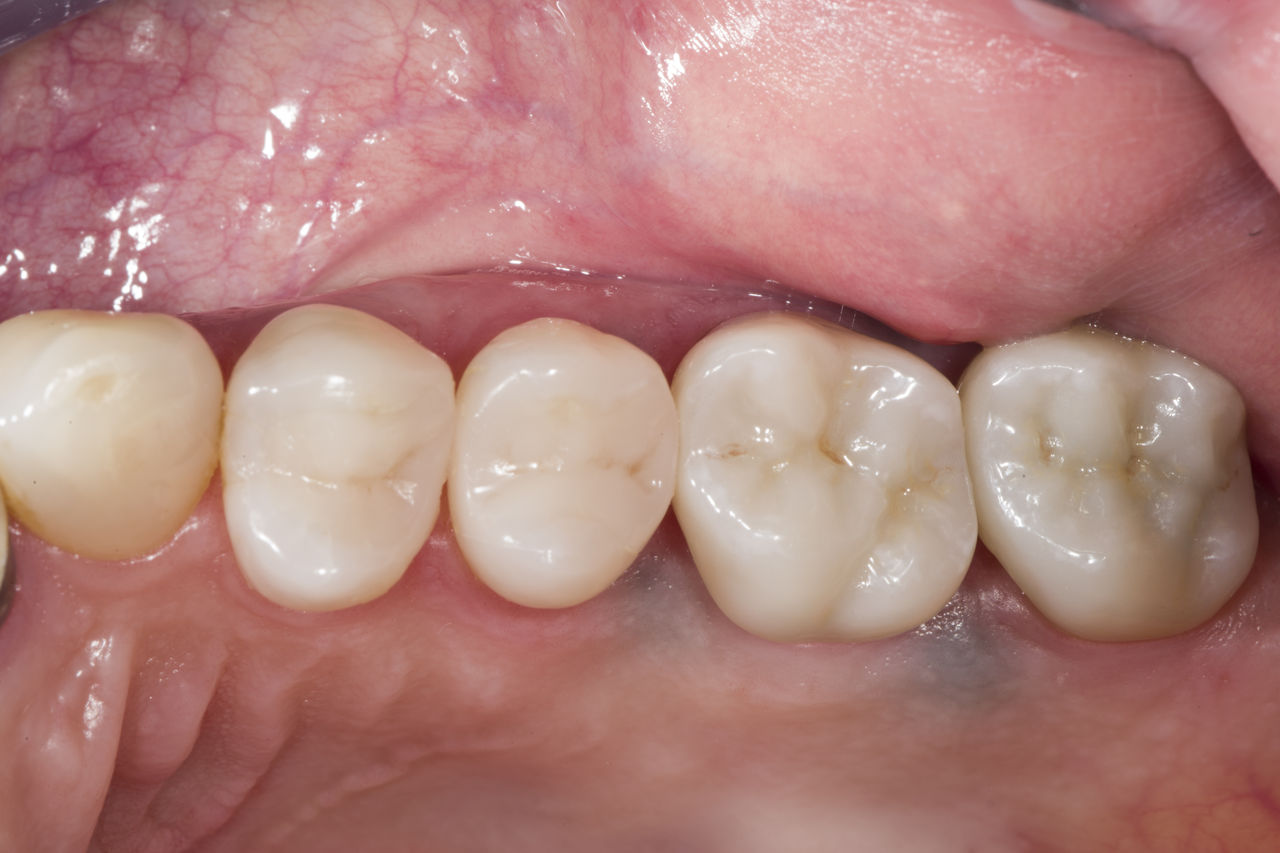

Restauration de la deuxième molaire mandibulaire en consultation

Couronne partielle CEREC Tessera

Une deuxième molaire mandibulaire sensible présentait des fissures ainsi qu’une restauration composite de classe I étendue sur la face vestibulaire. Conformément au concept mini-invasif, une couronne partielle CFAO a été planifiée, fabriquée et collée à l’aide du CEREC Tessera en une seule visite.

Avant : Restauration en amalgame défaillante nécessitant un remplacement. Patient se plaignant de sensibilité et dent présentant de multiples fissures.

Après : Restauration d’une couronne partielle CFAO réalisée en consultation avec la vitrocéramique CEREC Tessera Advanced Lithium-Disilicate.

Carlos Eduardo Sabrosa

Rio de Janeiro, Brésil